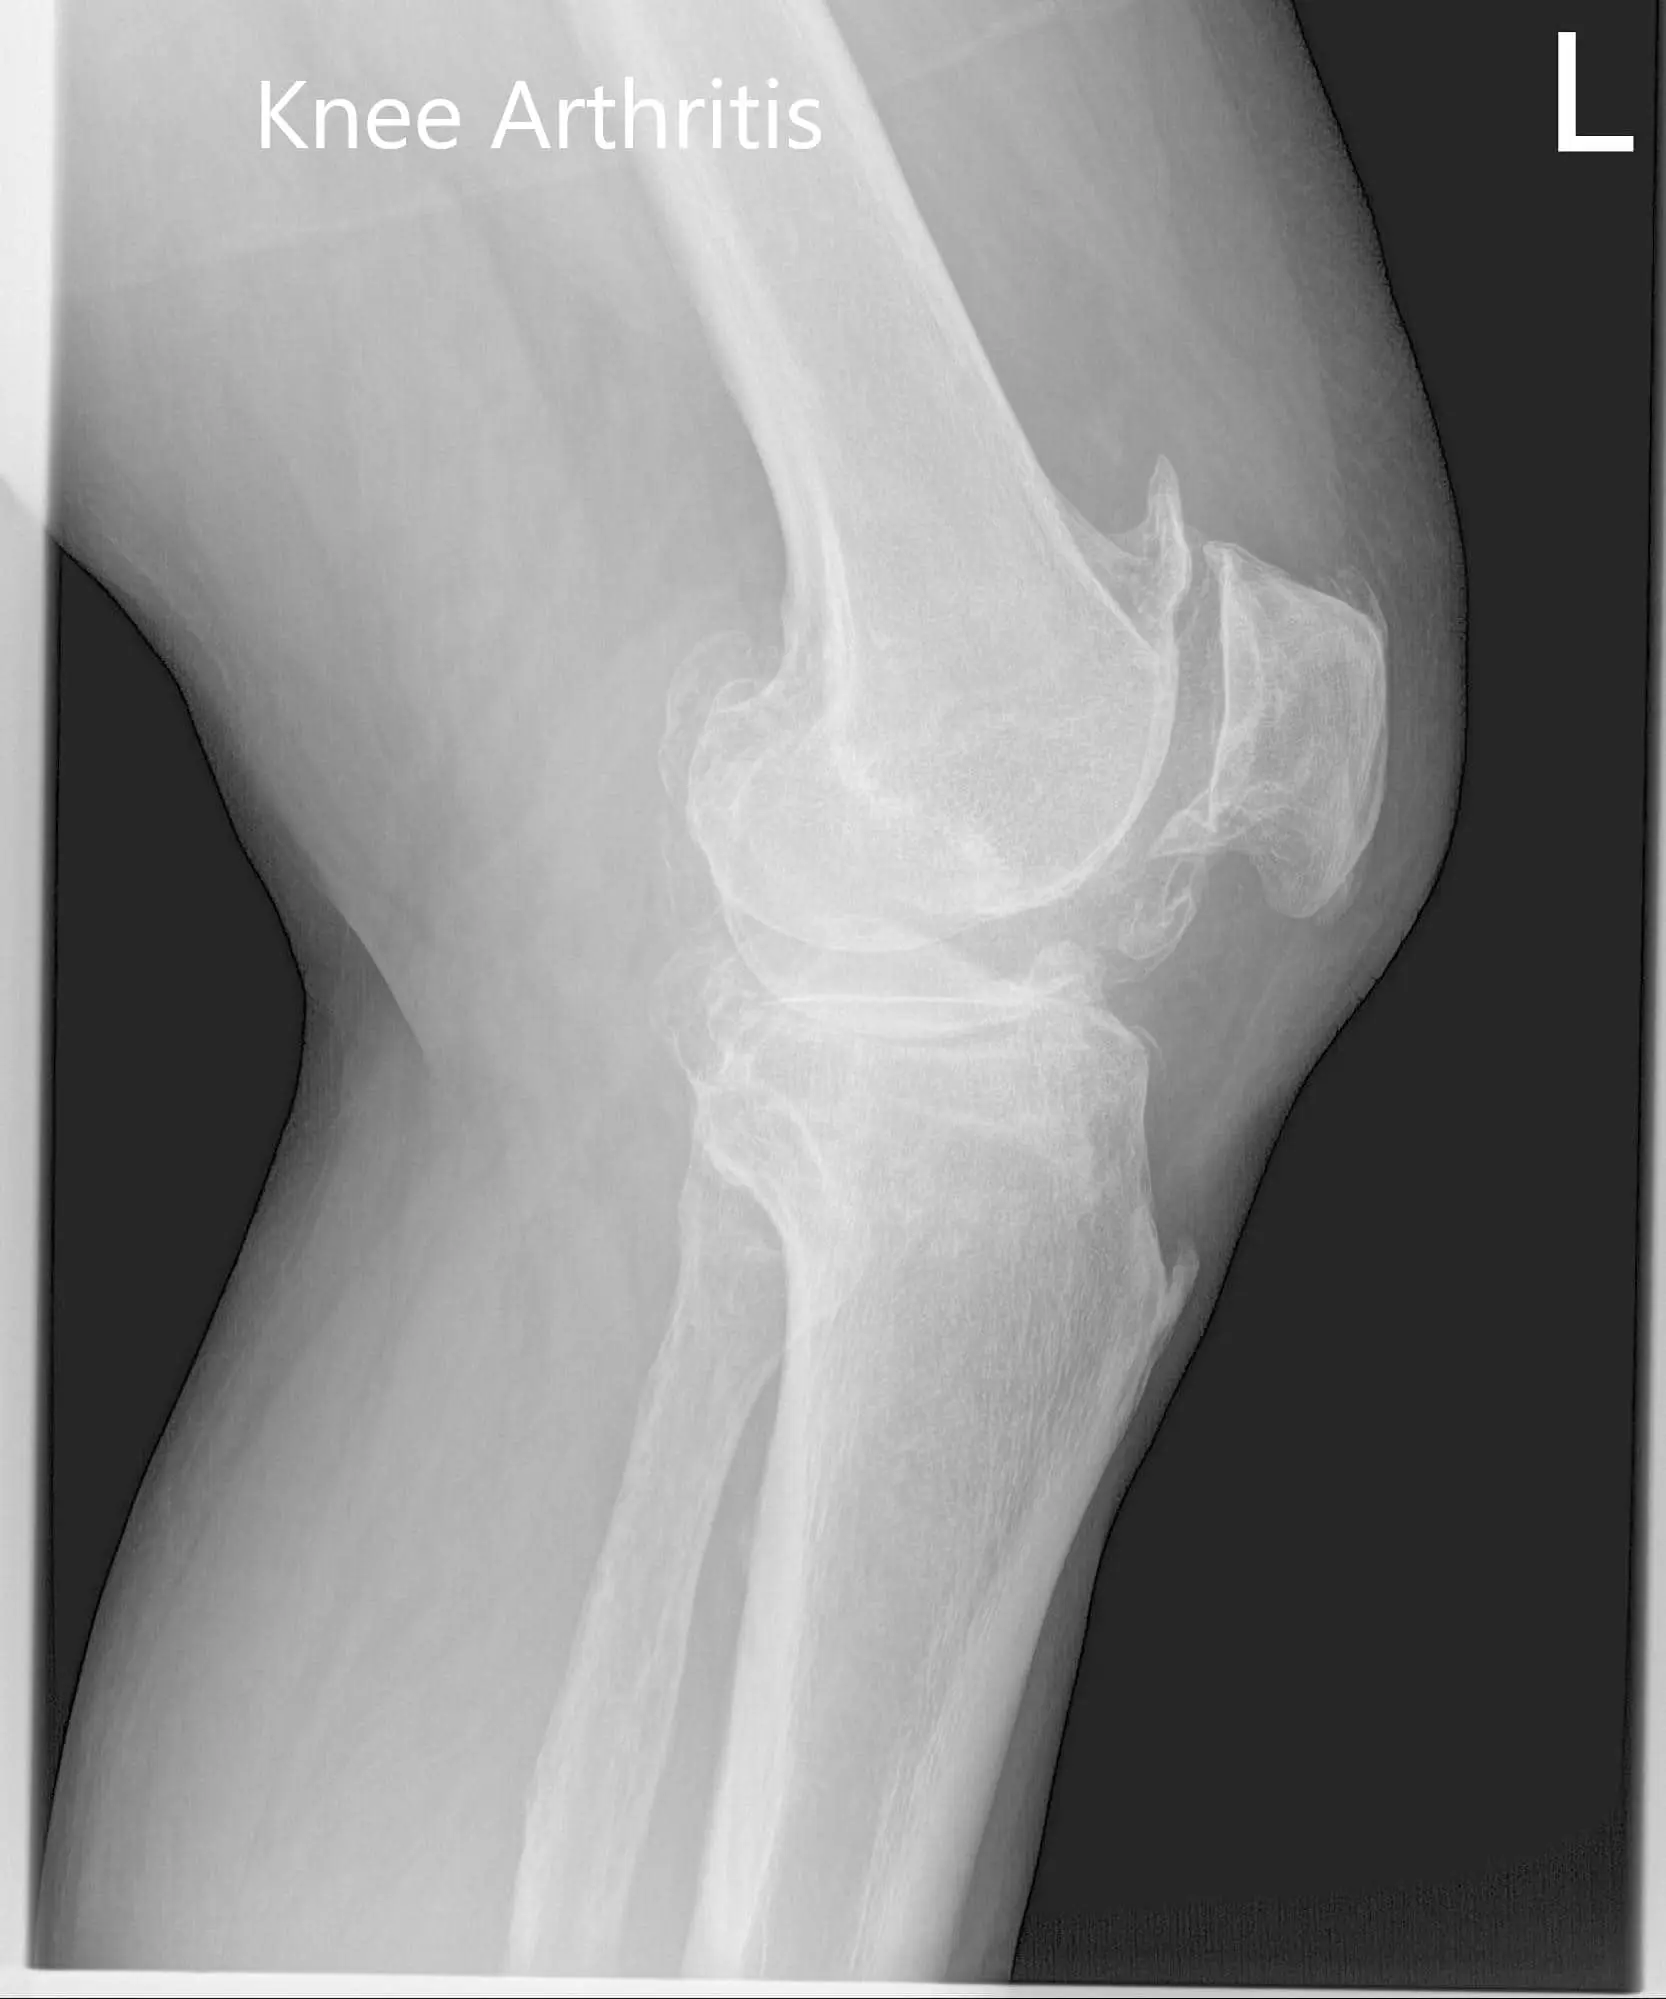

Considering his lifestyle limiting knee pain, various management options including both surgical and nonsurgical were discussed with him at length. He was considered a candidate for custom left knee total replacement. Risks, benefits and potential complications were discussed with him in detail. He agreed to the plan. Imaging studies revealed severe tricompartmental osteoarthritis of the left knee joint.

Preoperative X-ray of the left knee showing AP and lateral view of the knee with a skyline view of the patellaPreoperative X-ray of the left knee showing AP and lateral view of the knee with a skyline view of the patella - img 2Preoperative X-ray of the left knee showing AP and lateral view of the knee with a skyline view of the patella - img 3

Preoperative X-ray of the left knee showing AP and lateral view of the knee with a skyline view of the patella.